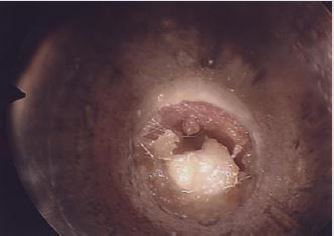

Six patients were identified: 66% (n=4) were male and 33% (n=2) were female. The female patients were twin sisters. Initial age at presentation ranged from 5 months to 4 years. 2 patients presented with X-linked ichthyosis. All patients had similar clinical presentations and clinical findings: hearing loss with no history of otorrhea or ear infections. Type B tympanograms and hearing loss was recorded. Otoacoustic emission (OAE) and middle ear reflexes (MER) were within normal range in all patients post procedure. All patients were booked for examination under general anesthesia (EAU). This revealed ear canal keratin plugs with some inflammatory skin changes in the absence of infective otitis externa or middle ear disease (Figures 1-3). Post operatively patients were reviewed in the outpatient department (OPD) at six weeks. If early ear canal keratinisation was observed at this time patients were commenced on olive oil ear drops and were re-scheduled for a second EUA and microdebridement of ears at a three-month interval. Preoperative tympanograms were type B. EUA results were similar demonstrating keratin plugs which underwent microdebridement. Post-operative tympanogram were within normal ranges.